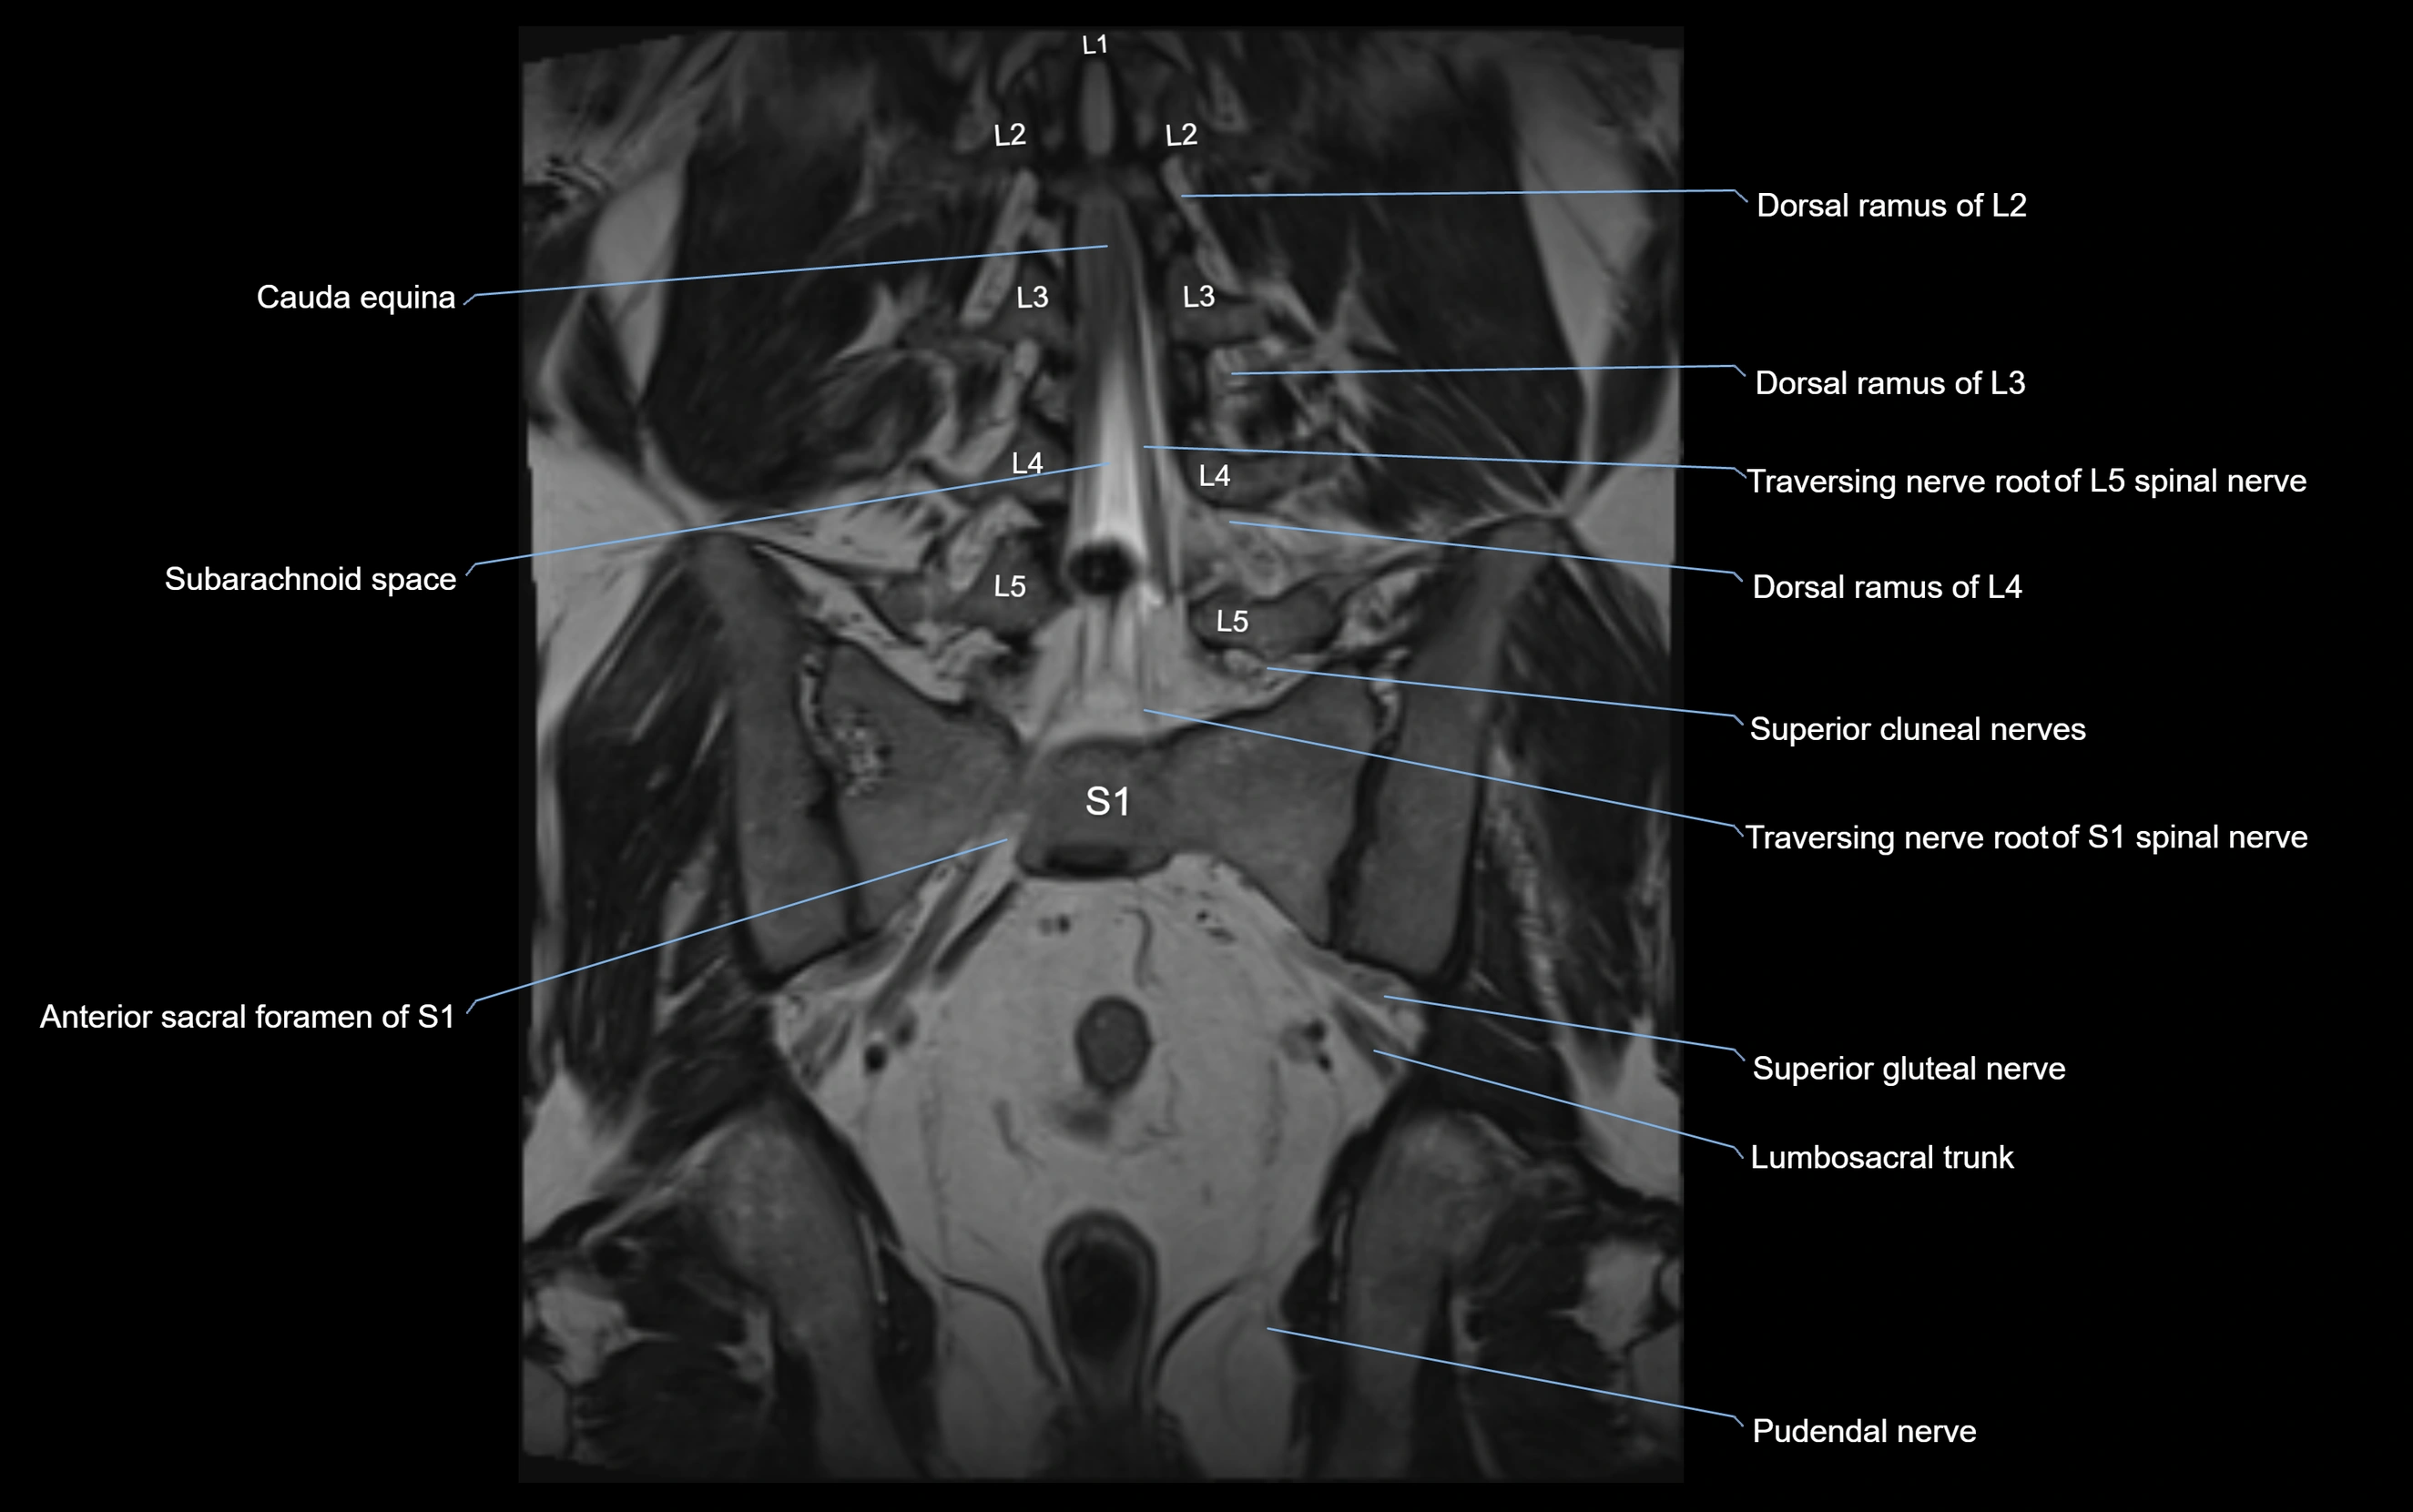

MRI Appearance

T1-weighted images:

• Nerve appears as a very thin low-to-intermediate signal intensity structure

• Surrounded by bright fat, aiding visualization

T2-weighted images:

• Nerve shows intermediate to mildly hyperintense signal compared to muscle

• Pathological involvement appears brighter

STIR (Short Tau Inversion Recovery):

• Normal nerve appears dark

• Inflamed or entrapped nerve appears bright hyperintense

T1 Fat-Sat Post-Contrast:

• Normal nerve enhances minimally

• Pathologic nerve (neuritis, entrapment, tumor infiltration) shows focal or diffuse enhancement

3D T2 SPACE / CISS:

• Nerve appears intermediate to mildly hyperintense compared to muscle

• Surrounded by bright fat or CSF, improving visualization

• Best sequence for mapping small pelvic nerves such as the anococcygeal